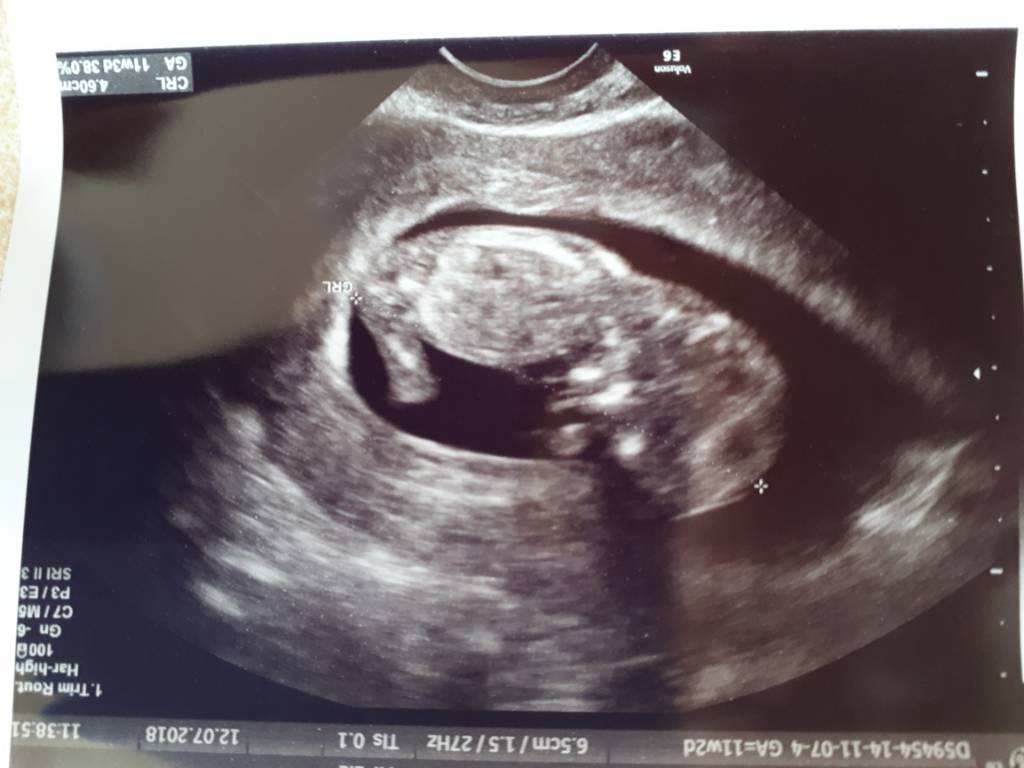

Screenshot_20180711-113107.jpg

Załączniki

• Screenshot_20180711-113107.jpg

57,3 KB · Wyświetleń: 248